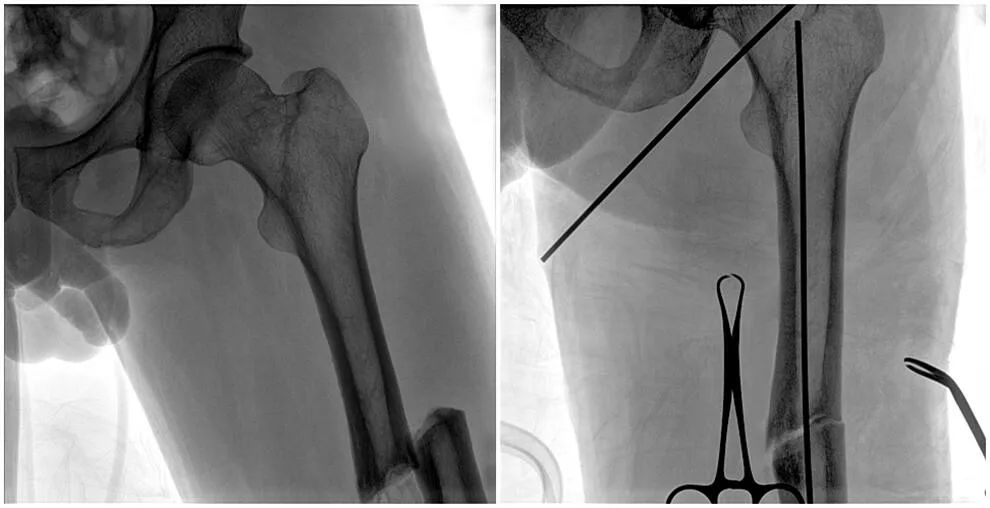

C形臂輔助手術(shù)過程

術(shù)中使用普愛醫(yī)療大平板一體式C形臂進行透視,判斷骨折情況及克氏針、髓內(nèi)釘?shù)冉饘僦踩胛锏奈恢茫M行調(diào)整。C形臂準確的術(shù)中定位,大大縮短了手術(shù)的時間,減輕了患者的痛苦,輔助手術(shù)順利完成。

在進行髓內(nèi)釘內(nèi)固定術(shù)時,醫(yī)生需要同時觀察到入釘點和骨折部位的情況,普愛醫(yī)療大平板一體式C形臂采用30CM×30CM的平板探測器,能夠呈現(xiàn)更廣闊的成像面積,滿足大部分長骨髓內(nèi)釘內(nèi)固定術(shù)的攝片需求。